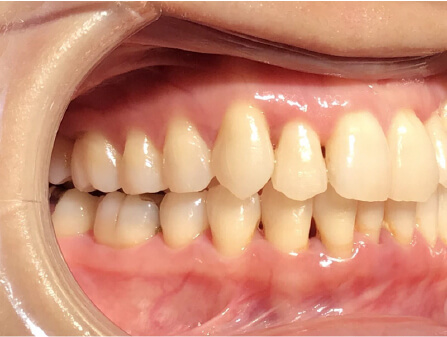

叢生の症例

17歳

/

女性

相談内容

カウンセリング・診断結果

治療内容・方法

全額アライナー矯正

術後の経過・現在の様子

クリアライナー使用

治療のリスク

痛み・歯根吸収・歯肉退縮・虫歯・後戻り

費用・治療期間

715,000円、2年10ヶ月

トレーニングなど